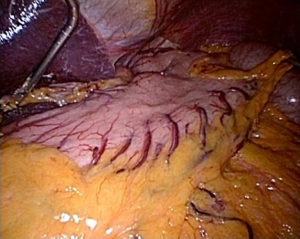

The esophagus is retracted anteriorly, and the pleura anteromedial to the ascending azygous vein is incised beginning at the level of the divided azygous arch and proceeding inferiorly down to the hiatus (Figure 26). The esophagus is the dissected off the descending aorta (Figure 27). The aorta is skeletonized from the aortic arch down to the hiatus exposing the left lung and left inferior pulmonary ligament (Figure 28). Most of the branches off the aorta can be managed with the ultrasonic shears, but it is prudent to leave a short stump of these branches on the aortic side to allow for placement of a clip or suture, if hemostasis with the ultrasonic shears is insufficient. Particularly troublesome are two small branches arising from the undersurface of the arch itself.

Once the descending aorta has been skeletonized, the division of the left pleura and the left inferior pulmonary ligament is completed proceeding from the lower chest superiorly (Figure 29A,B), skeletonizing the left inferior pulmonary vein and then dividing the left vagus nerve just above the left inferior pulmonary vein. The esophagus is then fully mobilized away from the aortic arch, LMB and distal trachea (Figure 29C). At this level, dissection is kept close to the esophagus to avoid injury to the left recurrent nerve. Once the infracarinal dissection is completed, the RMB, left main bronchus, carina, right and left inferior pulmonary veins, descending aorta and posterior pericardium have been skeletonized (Figure 30).